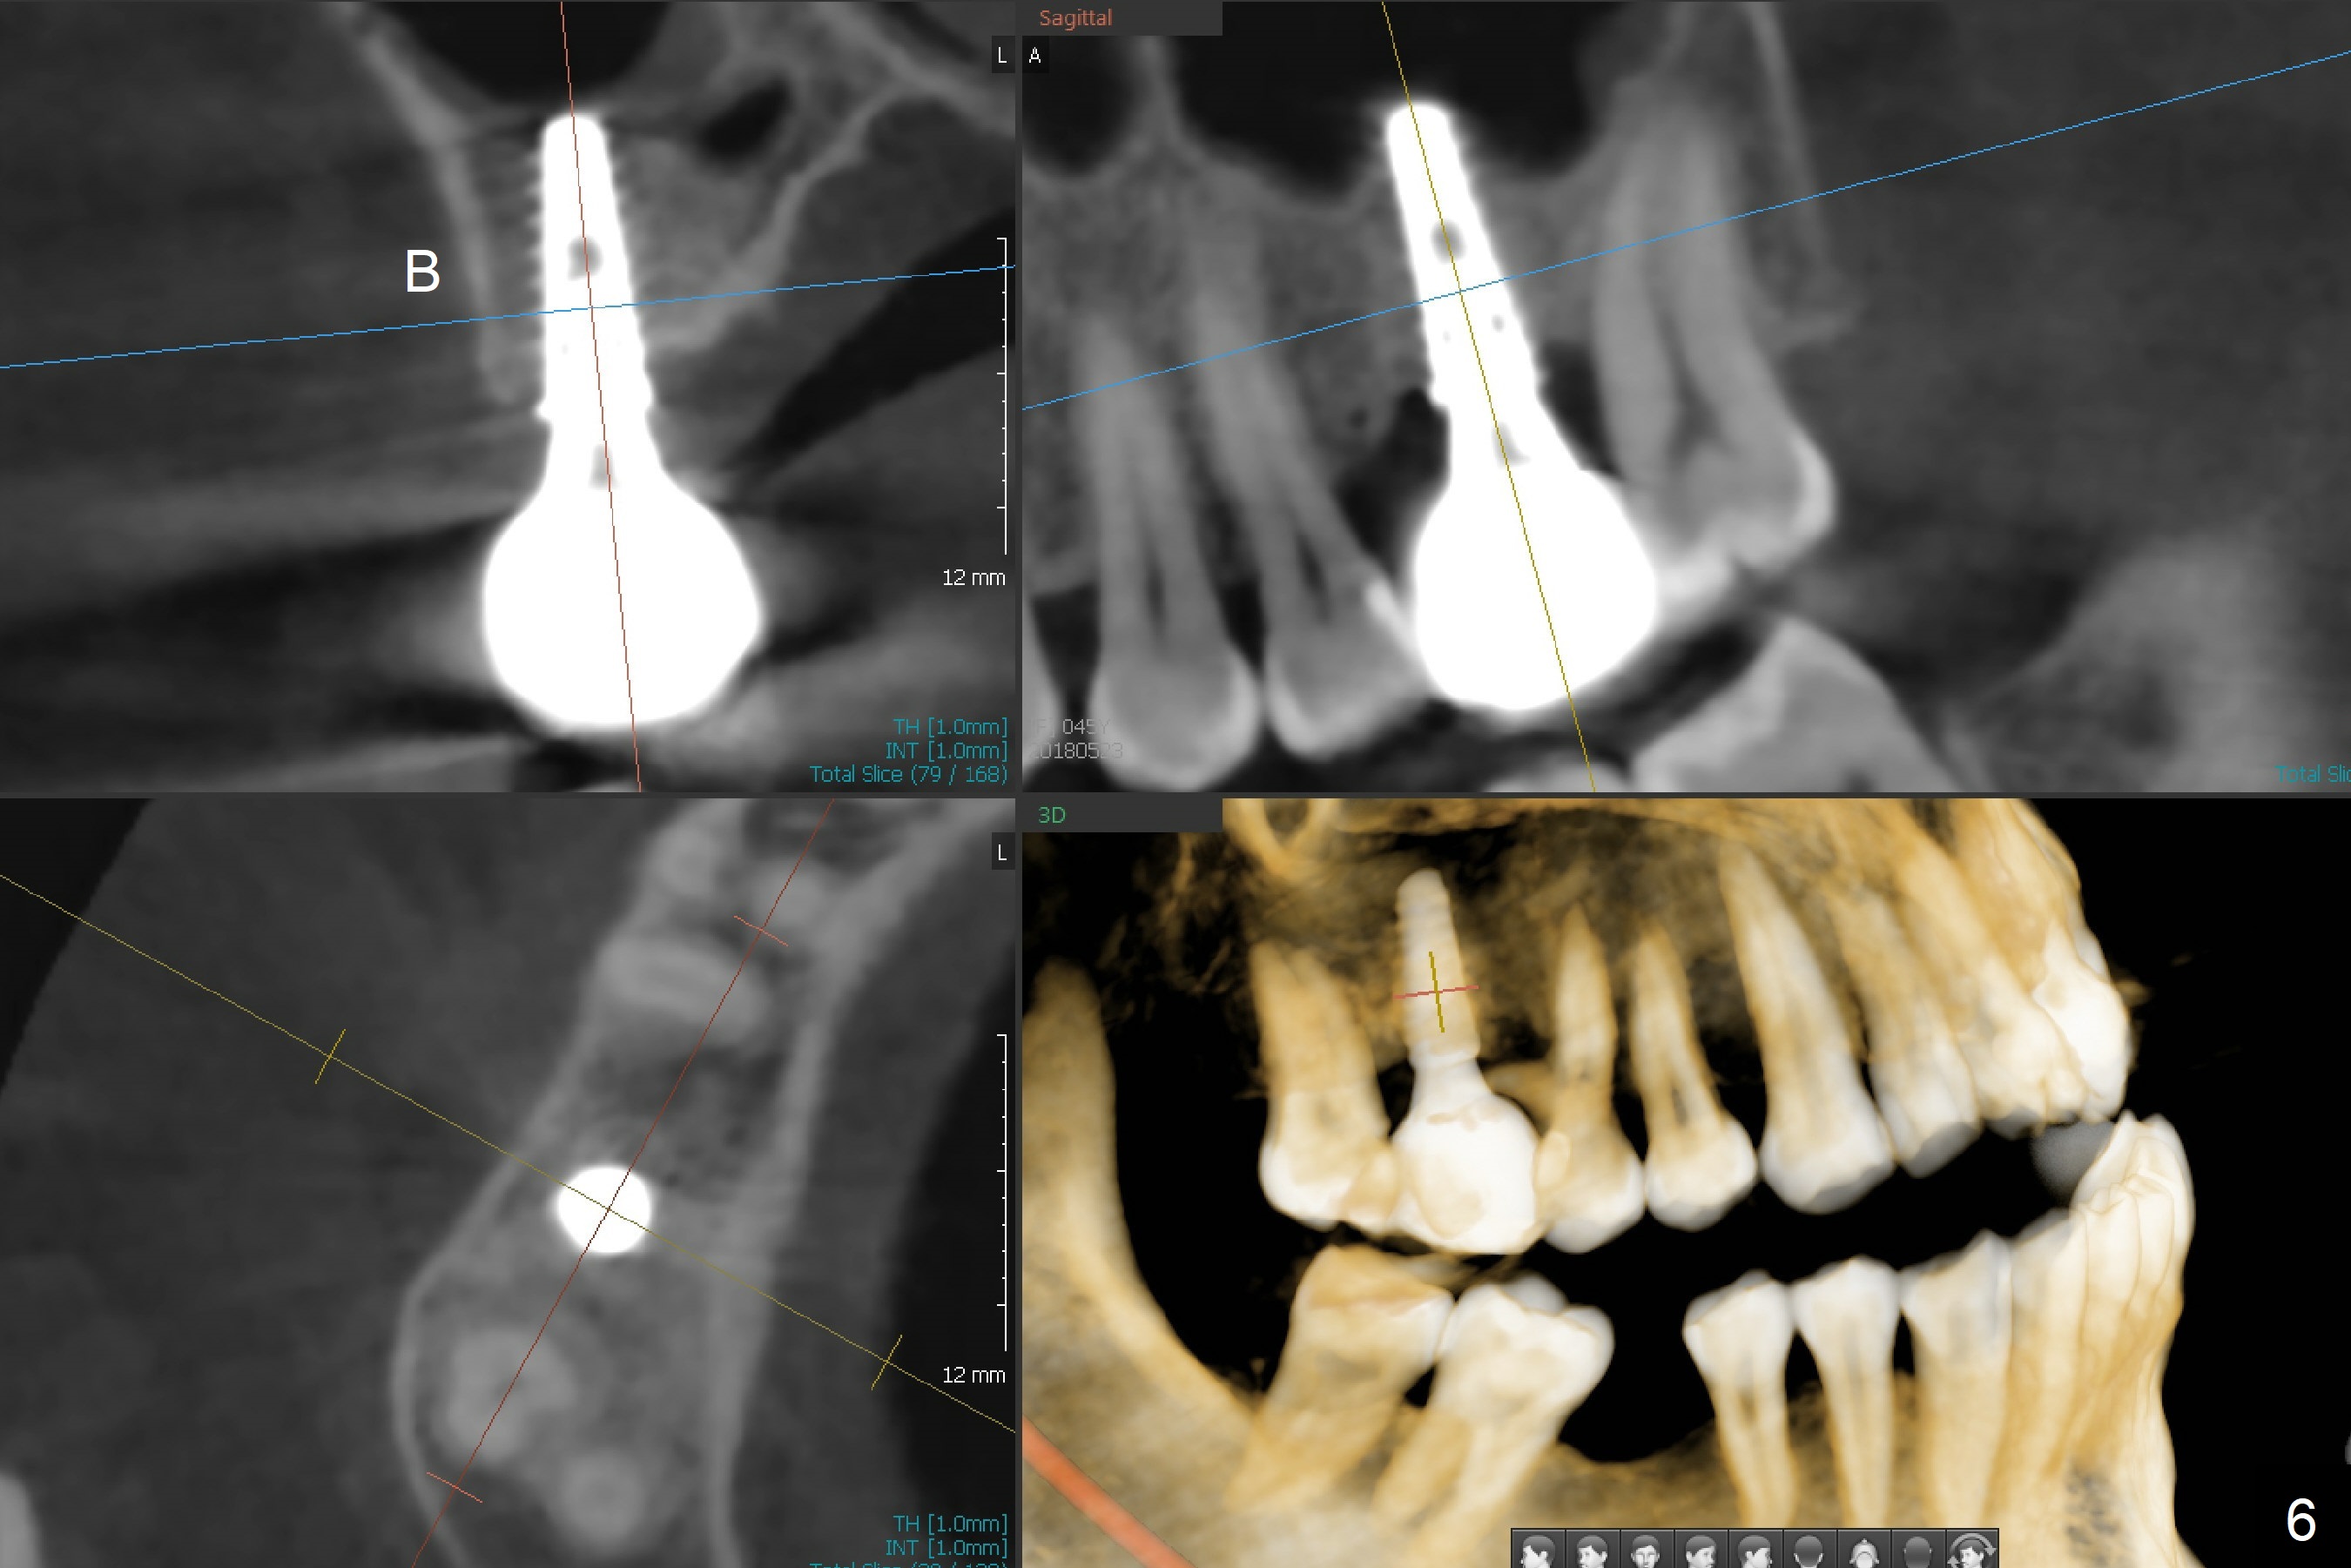

There are 2 sockets at #3 when the residual roots are extracted; osteotomy is established in the palatal one for 11 mm (gingival level; Fig.1), ~ 2 mm from the sinus floor (red dashed line). Following the last drill (3.8 mm) for 11 mm, a 4.5x11 mm dummy implant is placed 2 mm subgingival (Fig.2). In fact the sinus lift (red dashed line) is done by implant insertion, since the bone plug after Magic Drill is present in the apical portion of the osteotomy when the last drill is finished prior to implant placement.. After the dummy implant is removed, the definitive one (the same size) is placed with >50 Ncm, followed by placement of a 4.5x4(3) mm abutment and VeraGraft mixed with autogenous one (Fig.3 *). The most coronal portion of the socket is sealed with collagen plug. The latter is fixed in place by an immediate provisional. The mesial surface of the tooth #2 is reduced (Fig.4 <) prior to provisional fabrication. The implant is placed distal, which could be corrected by pushing the 2nd molar distal orthodontically. There is mild crestal bone loss nearly 8 months postop (Fig.5). An angled abutment (5x15 degrees, 3 mm cuff) is used before impression. CT is taken immediately post cementation (Fig.6 (8.5 months postop)). CT taken 8 months post cementation shows that the 4.5x11 mm implant barely passes the sinus floor (Fig.7). Return to Upper Molar Immediate Implant, Prevent Molar Periimplantitis (Protocols, Table), IBS, 30 19 Xin Wei, DDS, PhD, MS 1st edition 09/13/2017, last revision 01/31/2019